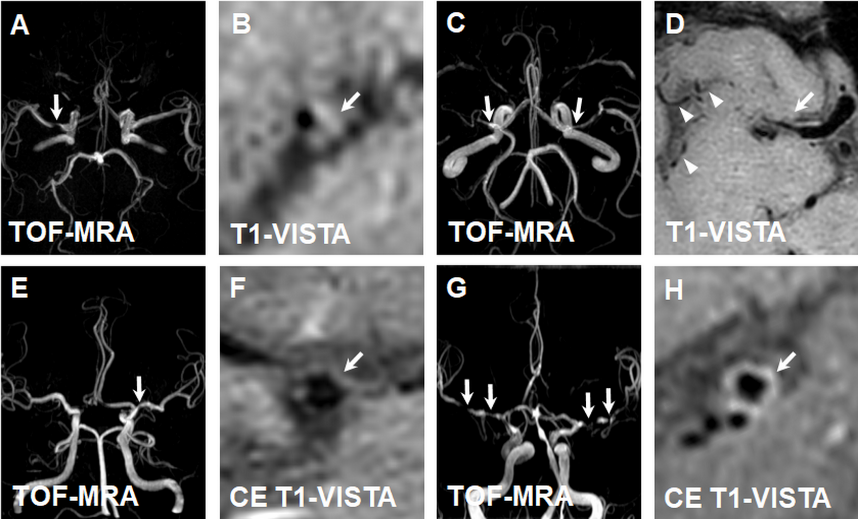

通过应用优化的T1-VISTA(西门子称为SPACE)序列对症状性颅内动脉狭窄患者的颅内动脉管壁进行成像研究发现,在158例患者中,导致颅内动脉狭窄的病因依次为动脉粥样硬化(82.3%)、烟雾病(8.8%)、动脉夹层(3.2%)、血管炎(0.6%)及其他原因不明疾病(5.1%)(图4)。本研究还发现动脉粥样硬化患者的低密度脂蛋白(2.8±1.1 mmol/L vs. 2.3±0.6 mmol/L, p = 0.022)和总胆固醇(4.4±1.4 mmol/L vs. 3.6±1.3 mmol/L, p = 0.019)水平显著高于非动脉粥样硬化患者。图5为颅内动脉粥样硬化、烟雾病、动脉夹层和血管炎患者的磁共振管壁特征。该研究结果提示,颅内动脉粥样硬化是导致国人症状性颅内动脉狭窄的最主要原因,其他非动脉粥样硬化疾病依次为烟雾病、夹层、血管炎和原因不明疾病。与非动脉粥样硬化性疾病相比,动脉粥样硬化患者表现为较高的低密度脂蛋白和总胆固醇水平。

图5 颅内动脉粥样硬化、烟雾病、动脉夹层和血管炎的磁共振影像特征

图A和B 为颅内动脉粥样硬化示例图,TOF-MRA可见右侧大脑中动脉狭窄(A,白箭),TI-VISTA图像可见右侧大脑中动脉偏心性管壁增厚(B,白箭)。图C和D为烟雾病示例图,TOF MRA可见双侧颈内动脉终末段重度狭窄闭塞(C,白箭),T1-VISTA提示右侧大脑中动脉近端管腔狭窄(D,白箭),走行区见多发侧枝血管形成(D,箭头)。图E和F为夹层示例图,TOF-MRA可见左侧大脑中动脉狭窄(E,白箭),TI-VISTA可见左侧大脑中动脉撕裂内膜片(F,白箭)。图G和H为血管炎示例图,TOF-MRA可见双侧大脑中动脉多发狭窄(G,白箭),TI-VISTA示左侧大脑中动脉向心性管壁增厚,并呈明显强化(H,白箭)。